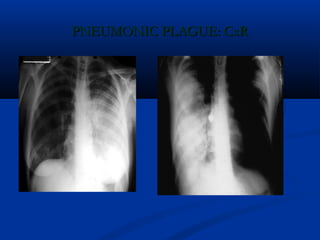

PNEUMONIC PLAGUE: CxRPNEUMONIC PLAGUE: CxR

PLAGUE: CONTROLPLAGUE: CONTROL